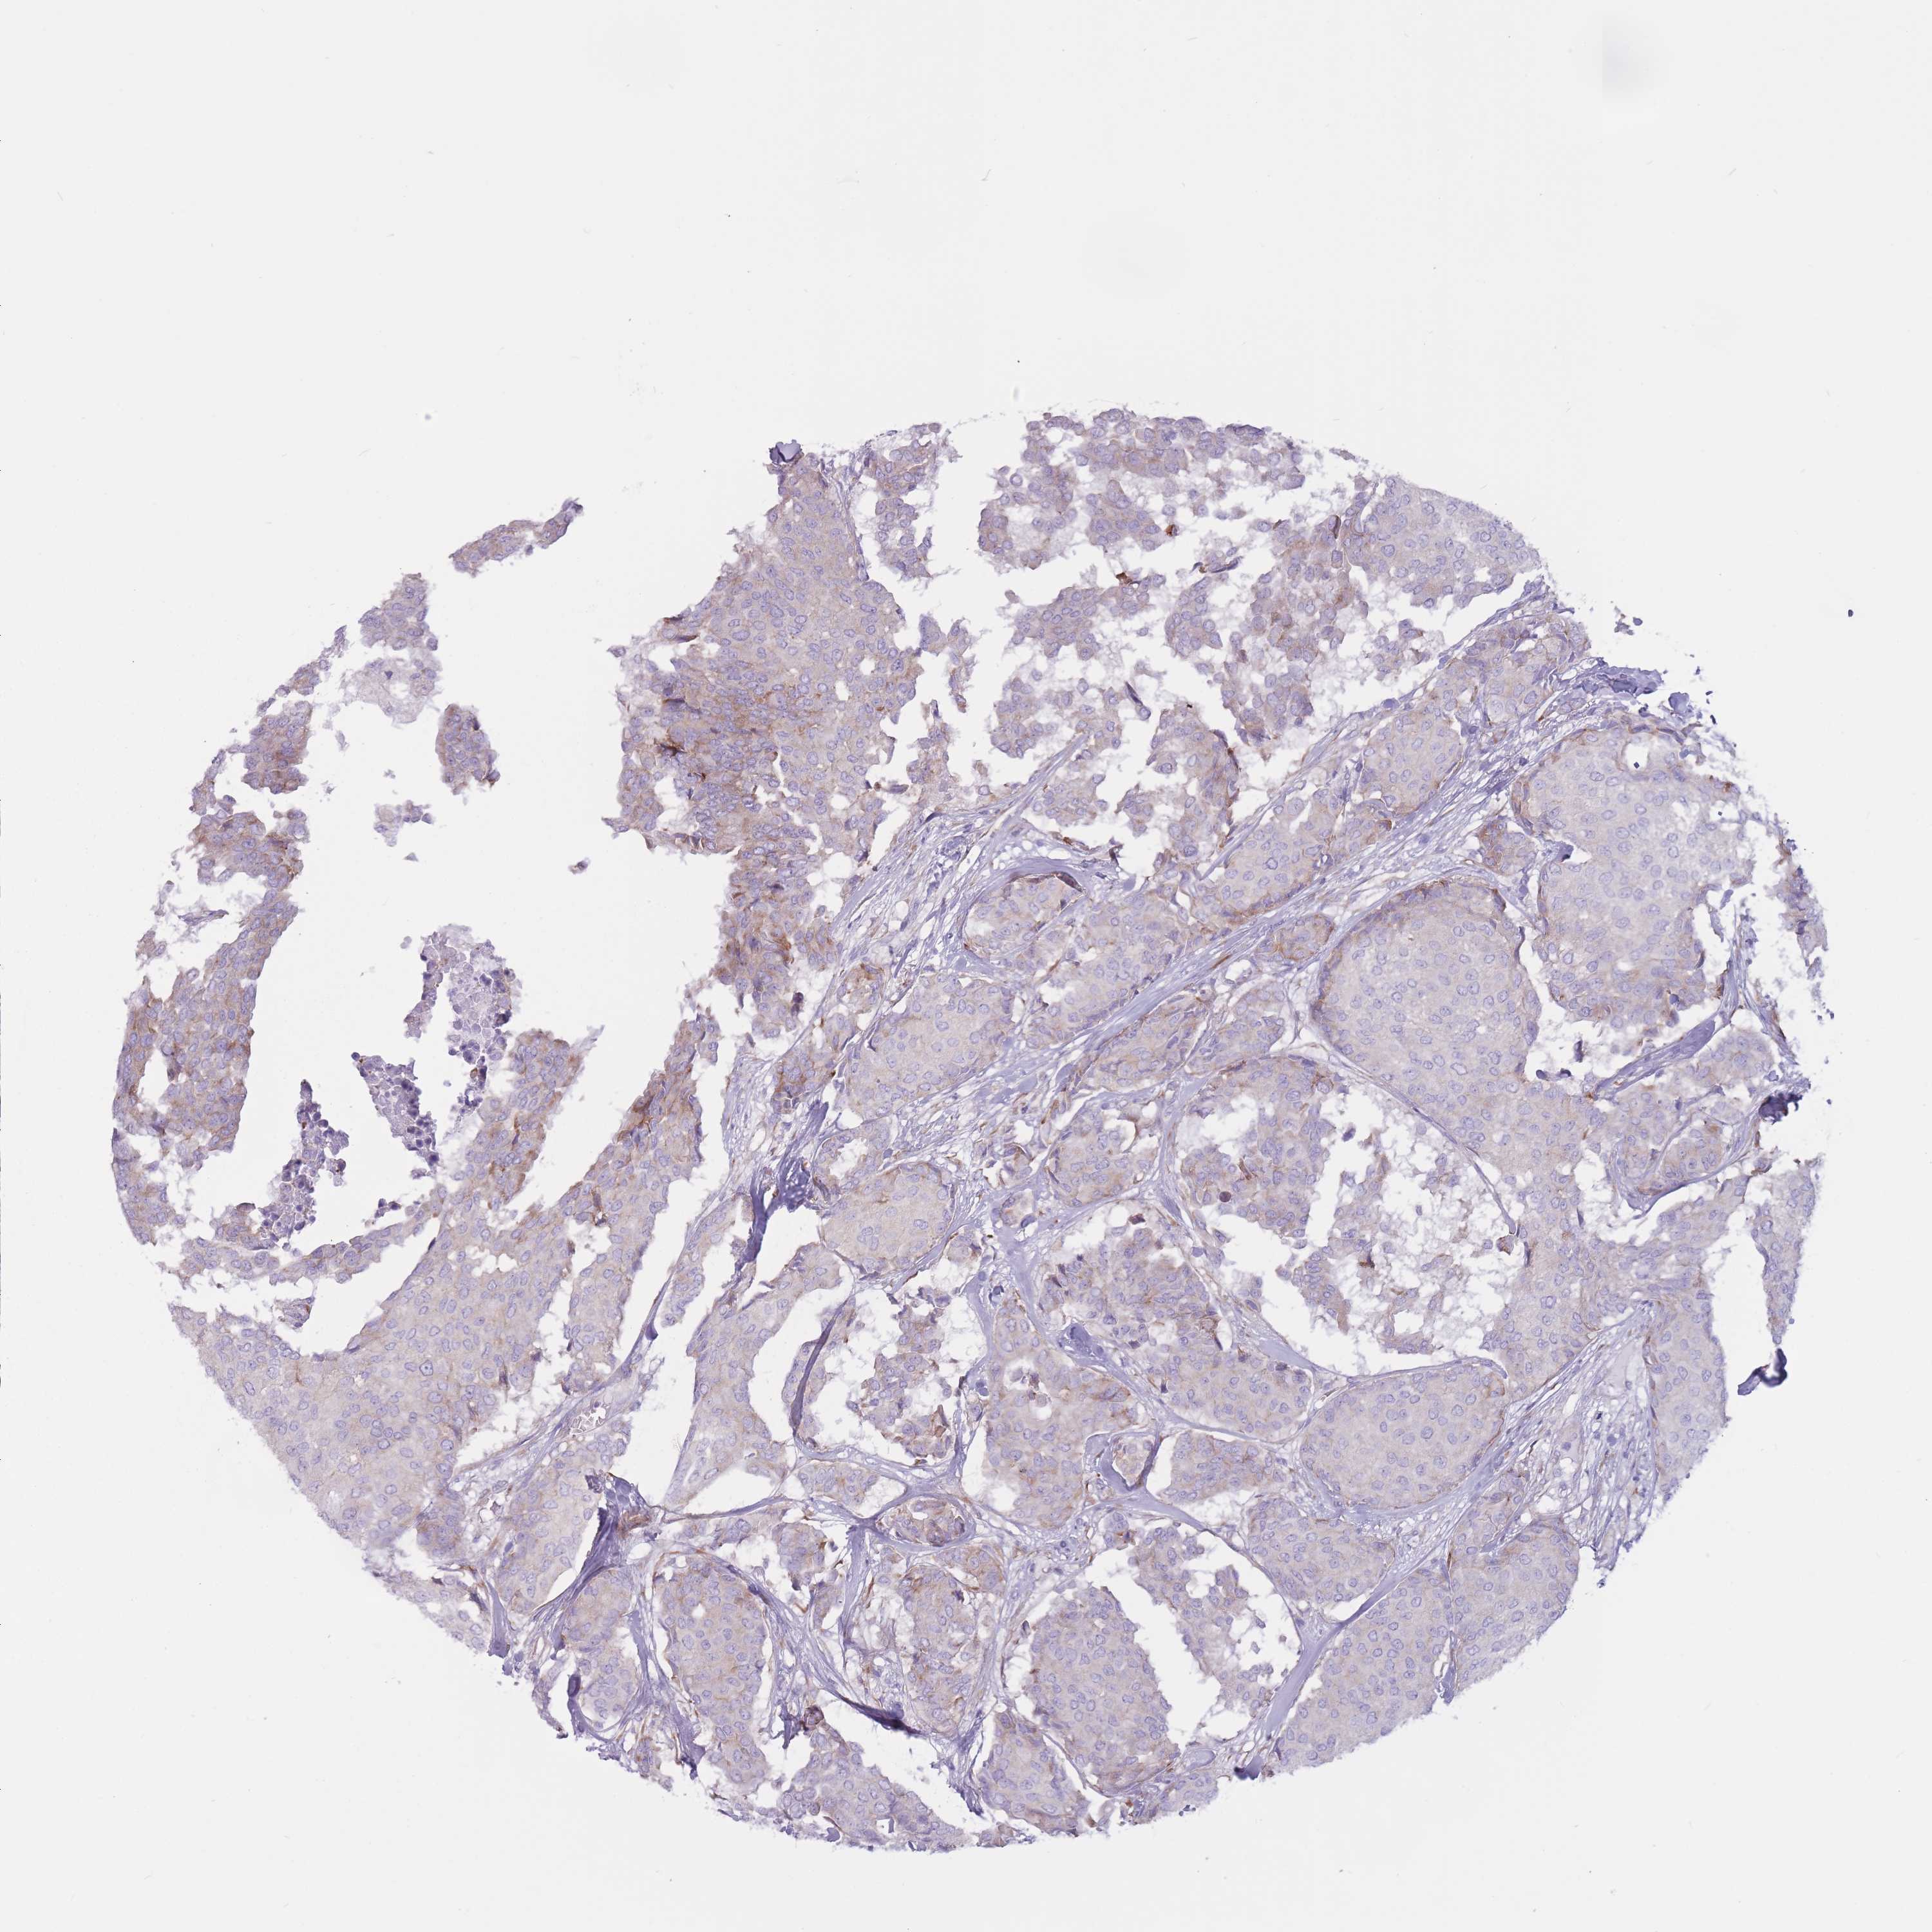

BRCA TCGA BRCA VALIDATION PROTEIN EXPRESSION

Breast cancer

Human cancer

Breast invasive carcinoma